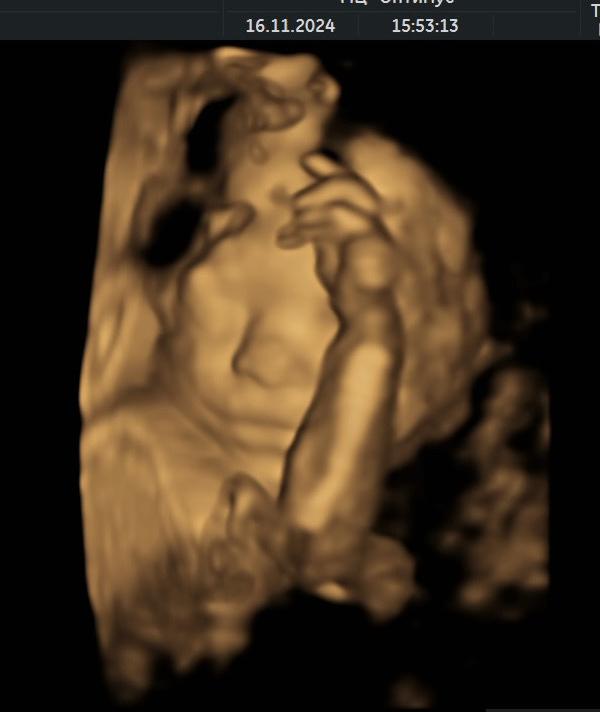

Арсений передает привет, закрывался руками, потом повернулся спиной: что это значит?

post image 1

Арсений передает привет, закрывался руками, по итогу повернулся спиной 😅